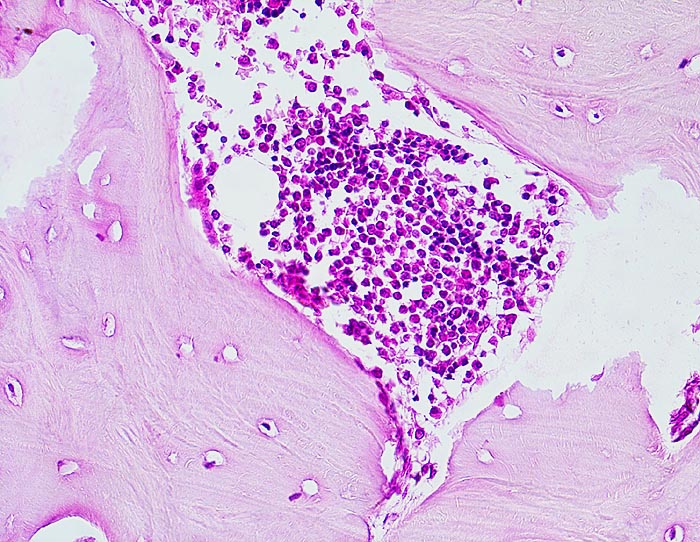

Normale Spongiosa

Normale Spongiosa mit wenig Osteoblasten an der Bälkchenoberfläche. Innerhalb der Spongiosa sind Osteozyten in ihren Lakunen erkennbar. Auf diesem Bild sind keine Osteoklasten zu sehen, die sich normalerweise an der Knochenoberfläche befinden und in Einbuchtungen liegen (sog. Howship Lakunen).